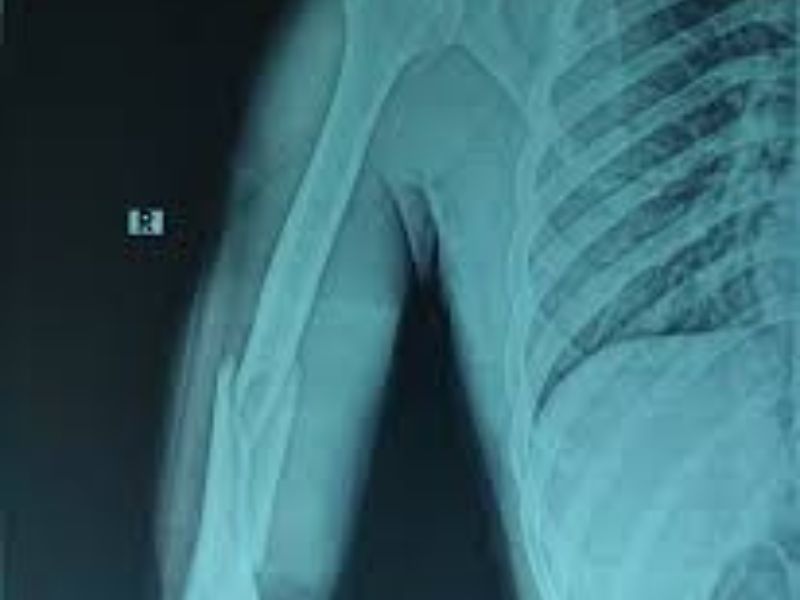

U xương sụn thường phát triển chậm, gây đau hoặc biến dạng nhẹ ở khu vực xương bị ảnh hưởng. Khi khối u lớn, bệnh nhân có thể cảm thấy khó chịu hoặc bị hạn chế vận động. Trên ảnh chụp X-quang, u xương sụn cho thấy hình ảnh nấm sụn có cuống, phát triển gần hành xương.

- Chụp X-quang: Là phương pháp chẩn đoán hình ảnh đầu tiên và phổ biến nhất để phát hiện bất thường trong cấu trúc xương, giúp xác định vị trí khối u, hình dạng, mật độ và mức độ ảnh hưởng đến mô xương xung quanh. Hình ảnh X-quang có thể cho thấy các dấu hiệu như vùng mất xương (tiêu xương) hoặc tạo xương bất thường.